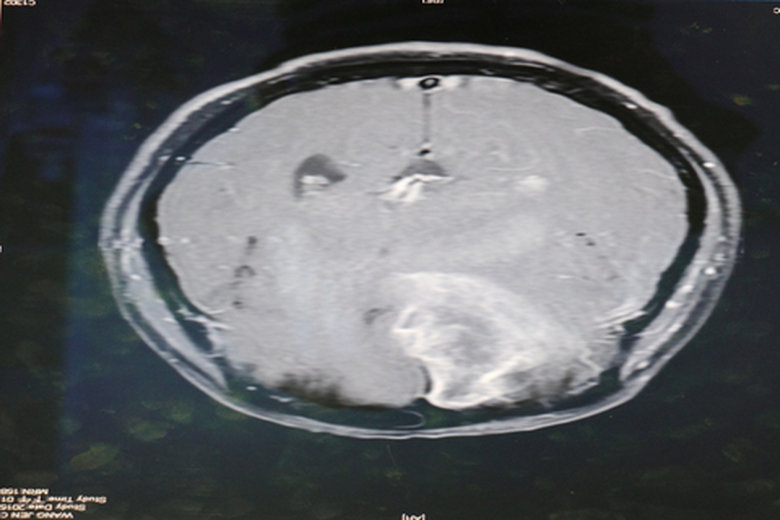

為清除位在大腦功能區附近的腫瘤,術中GPS導航,降低腦瘤切除風險。 (圖/嘉義基督教醫院提供)

【新唐人亞太台 2016 年 07 月 18 日訊】在醫界中,腦瘤切除被喻為最棘手的手術,如果稍有失準,就可能破壞神經系統,造成癱瘓。嘉義基督教醫院日前利用術中GPS導航,讓開腦手術更安全,大大減少手術無法預期的神經系統傷害,以及併發症及死亡率。

51歲的李女士經常頭暈不舒服,一天工作時突然左半身沒力,至嘉基檢查後發現是罹患乳癌併腦轉移。位於大腦右側頂葉運動區附近,由於腫瘤壓迫,導致左側肢體偏癱。嘉基神外醫療團隊利用術前立體定位導航系統,安全將腫瘤移除,術後病患左側肢體肌力顯著進步,能自行走路進食。

嘉義基督教醫院醫師陳昱豪表示:腦瘤切除手術十分棘手,稍有誤差就可能破壞神經系統,造成功能性問題。尤其是膠質瘤,邊緣非常不清楚,甚至顯微鏡下仍無法區分,這時後術中GPS導航系統-立體定位導航手術就非常的重要。

立體定位放射手術(伽傌刀或電腦刀)前先將影像與電腦結合,定位出腦瘤的位置及範圍,也可以在術中利用紅外線攝影機偵測手術器械位置,再轉到腦部影像,可以知道手術器械與腦瘤的相關位置。與傳統放射線治療的主要差別,是可精準的將高能量放射線直接打在腫瘤病灶上,誤差小於1mm,減少對正常組織的傷害大為減少手術無法預期的神經系統傷害,同時降低併發症及死亡率。